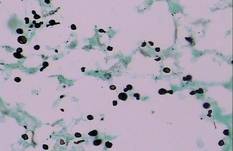

| Figure 4. Black-colored, ovoid, budding spores of Cryptococcus were seen (Gomori methenamine-silver, original magnification ×100). |

Gram stain and a potassium hydroxide (KOH) mount of a smear from the ulcerated lesion on the neck showed encapsulated budding spores. Histopathologic study of hematoxylin and eosin–stained sections from the noduloulcerative lesion on the shoulder demonstrated irregular acanthosis in the epidermis; a granulomatous reaction comprised of lymphocytes, histiocytes, neutrophils, plasma cells, and few giant cells; and a gelatinous tissue reaction with numerous ovoid encapsulated spores (Figure 3). Gomori methenamine-silver stain revealed black-colored, ovoid, budding spores (Figure 4), and periodic acid–Schiff stain also revealed narrow-based budding spores. Mucicarmine staining showed multiple red-colored, budding, capsulated spores (Figure 5). A culture on Sabouraud dextrose agar confirmed growth of C neoformans. Examination of sputum by KOH mount and india ink preparation demonstrated encapsulated spores of Cryptococcus. India ink staining of cerebrospinal fluid and urine was negative for Cryptococcus. Cerebrospinal fluid cytochemistry was within reference range. The final diagnosis was disseminated cryptococcosis in the setting of uncontrolled DM.